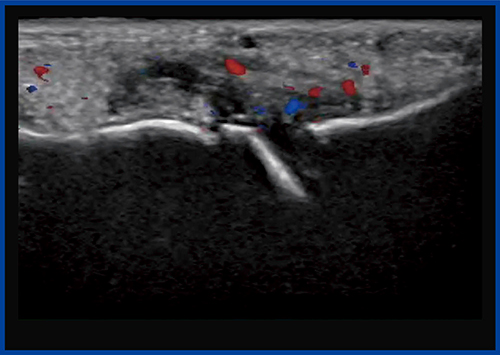

●症例2:第2趾MTP関節炎

症例2は,Bモードにて中足骨と基節骨の関節の腫れと,関節液の貯留が確認され,一部に初期の骨びらんが疑われた(図5)。カラードプラ(図6)では,滑膜には豊富な血流が見られるが,骨びらんが疑われる部位にはほとんど血流が認められなかった。一方,SMI(図7)では,骨びらんの周囲から骨の中に流入する血流がわずかに認められた。

本症例は,未確定ではあるがリウマチが疑われる。通常,リウマチの診断はカラードプラを用いて行われるが,カラードプラでは滑膜の血流状態だけを見ているため,SMIを加えることで,リウマチ発生初期から見られる骨びらんを早期に評価できるようになると期待される。

図6 症例2のカラードプラ画像

滑膜には豊富な血流が見られるが,骨びらん周囲にはあまり血流が見られない。

図7 症例2のSMI画像

骨びらん周囲から骨の中に流入する血流をわずかに認める。